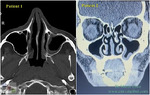

| Rhinology Serpentine Sign: evidence of airway compensation in patients with empty nose syndrome Sep 9, 2025 P-W Wu, F T-N Yu, T-J Lee, C-C Huang, P-H Chang, C-C Huang This study aimed to evaluate the presence of Serpentine Signs on computed tomography (CT) images and its impact on the clinical symptoms in patients with empty nose syndrome (ENS). METHODS: A retrospe... Journal Article |